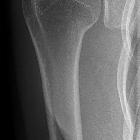

Weichteilfalten